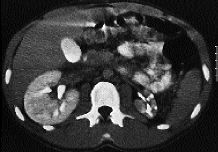

Luxación dorsal del trapezoide

Dorsal dislocation of the trapezoid